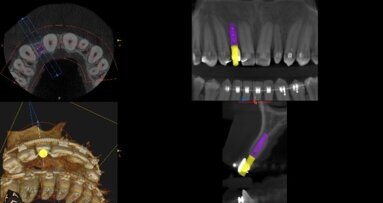

Pacjent, lat 27, także zgłosił się do tutejszej poradni chirurgii stomatologicznej celem kontroli stanu miejscowego po przeprowadzonej 3 miesiące wcześniej ekstrakcji zęba 16. Powtarzające się okresowe dolegliwości bólowe oraz konieczność przyjmowania leków przeciwbólowych skłoniły pacjenta do szukania pomocy specjalistycznej. Pacjent poddała się badaniu rtg pantomograficzne we własnym zakresie. Wykazało ono, iż w okolicy 16 pozostawiono fragment korzenia podniebiennego i zmianę okołowierzchołkową o charakterze torbieli korzeniowej. Ponadto, pomiędzy fragmentem korzenia podniebiennego zęba 16 a wierzchołkiem korzenia zęba 15 stwierdzono ciało obce o przybliżonych wymiarach 8:3 mm i wysyceniu sugerującym obecność metalu. W badaniu klinicznym okolica 16 nie wykazywała zmian zapalnych, rana poekstrakcyjna była prawidłowo wygojona.

Wykonano planową rewizję okolicy 16. W znieczuleniu miejscowym 4% chlorowodorkiem artykainy wykonano cięcie na szczycie wyrostka zębodołowego i odpreparowano płaty obustronnie. Po zniesieniu fragmentu blaszki kostnej uzyskano dostęp do korzenia podniebiennego, który usunięto w całości. Wyłuszczono także zmianę o charakterze torbieli, co potwierdzono badaniem histopatologicznym. Następnie odnaleziono ciało obce, które było położone w tkance kostnej, podniebiennie od wierzchołka korzenia zęba 15. Usunięty fragment metalu okazał się końcówką roboczą dźwigni ekstrakcyjnej (prawdopodobnie Beina). Ranę zaopatrzono szwami 4-0 monofilament, które usunięto po 7 dniach. Pacjentowi zalecono stosowanie ketoprofenu w dawce 2 x 50 mg p.o. przez 5 dni oraz miejscowo płukanie jamy ustnej chlorheksydyną. Po wykonanym zabiegu dolegliwości bólowe ustąpiły. Kontrola po 4 miesiącach wykazała prawidłowe zagojenie rany i przebudowę tkanki kostnej.